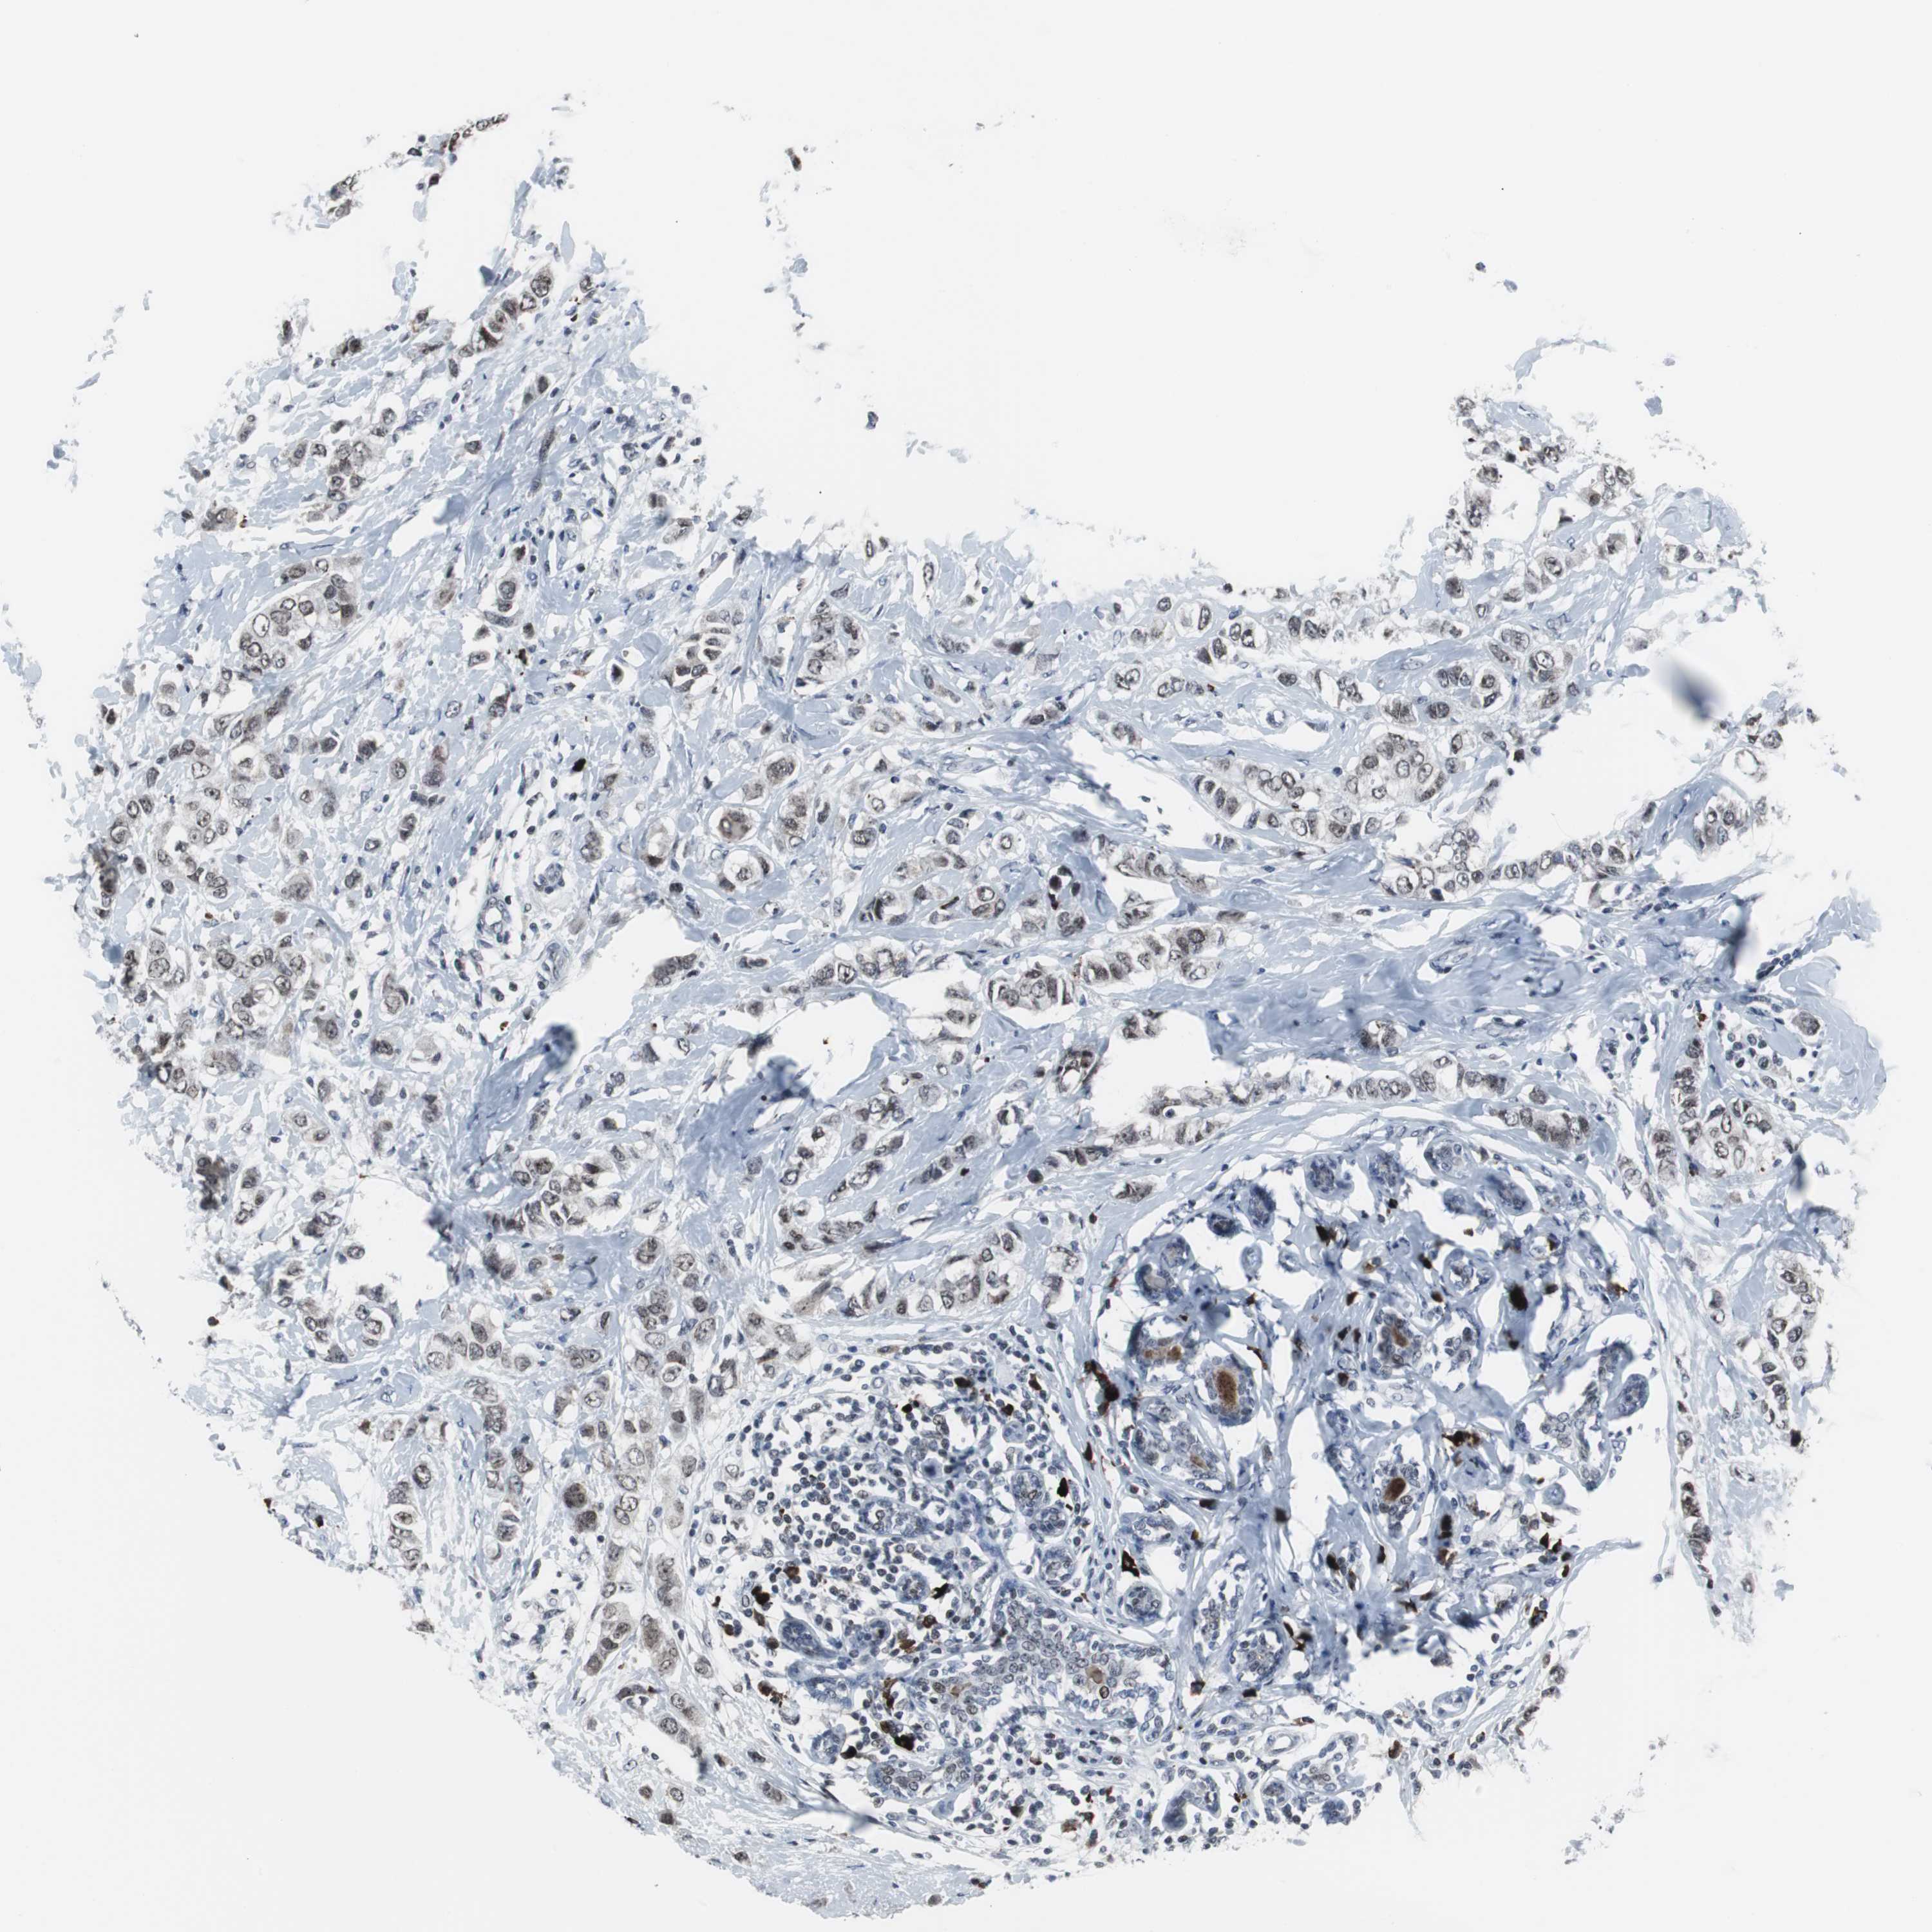

BRCA TCGA BRCA VALIDATION PROTEIN EXPRESSION